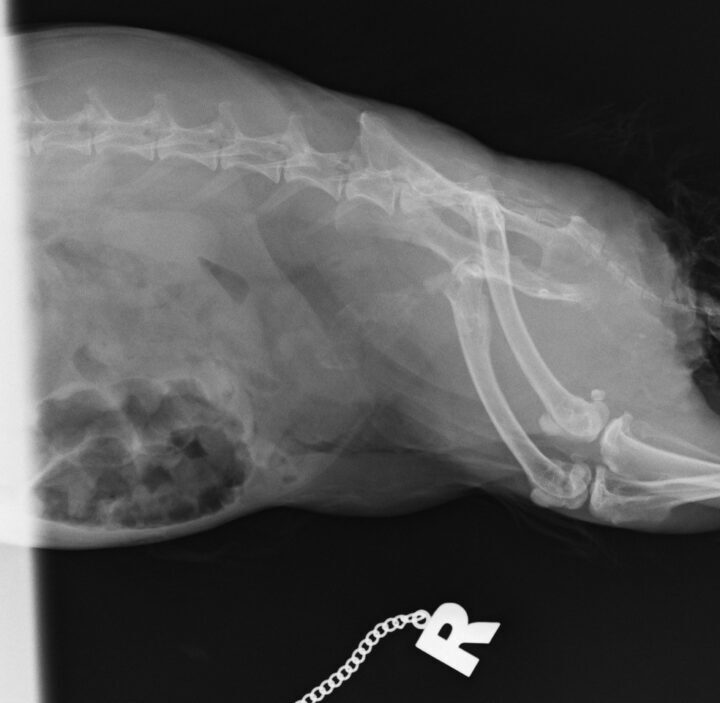

Diagnosis is typically based on clinical signs, physical examination, urinalysis and imaging. The urine may appear cloudy or contain visible sediment. Radiographs can help assess the amount of sludge present and rule out other issues such as urolithiasis (Figure 2). Urinary ultrasound is another useful tool, providing a more detailed view of the bladder wall and sludge accumulation.

Management of bladder sludge involves addressing the underlying dietary issues, such as reducing high-calcium foods like alfalfa hay and ensuring a diet of mostly grass hay, leafy greens and a balanced pellet. In more severe cases, medical management may include diuretics to encourage urinary excretion, as well as pain management with non-steroidal anti-inflammatory drugs (NSAIDs) and potassium citrate to attempt to acidify the urine to prevent precipitation of calcium salts (Hoefer and Latney, 2009). In rare cases, if the sludge leads to bladder distension or obstruction, or if the resultant bladder pain causes gastrointestinal stasis episodes, physical intervention may be required. In some cases, catheterisation of the bladder and flushing with warm sterile saline can remove the abnormal bladder contents (Figure 3). In more severe cases, cystotomy and removal of the bladder contents may be required.

The clinical signs of urolithiasis in rabbits include haematuria, dysuria, frequent urination and stranguria. In some cases, the stones can cause a complete obstruction of the urinary tract, which is a medical emergency (Circella et al., 2021). Diagnosis is confirmed through radiographs, where the stones will appear as radiopaque structures, or via ultrasound, where uroliths result in acoustic shadowing.